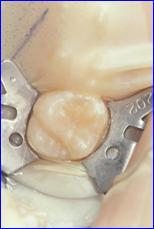

シーラントというのは、あらかじめ、この溝を合成樹脂で埋めてしまう予防処置です。

シーラントは歯に接着するレジンという材料を用いて行うことが多く、きちんと歯質に接着させるためには、薬剤によって歯面を処理後、十分乾燥した状態で溝を覆うように塗布する必要があります。

当院ではラバーダムという方法を用いて防湿を行ってシーラントを行っています。

治療前 シーラント後